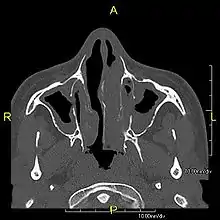

The main consequence of impaired ciliary function is reduced or absent mucus clearance from the lungs, and susceptibility to chronic recurrent respiratory infections, including sinusitis, bronchitis, pneumonia, and otitis media. Progressive damage to the respiratory system is common, including progressive bronchiectasis beginning in early childhood, and sinus disease (sometimes becoming severe in adults). However, diagnosis is often missed early in life despite the characteristic signs and symptoms.[1] In males, immotility of sperm can lead to infertility, although conception remains possible through the use of in vitro fertilization, there also are reported cases where sperm were able to move.[2] Trials have also shown that there is a marked reduction in fertility in female sufferers of Kartagener's syndrome due to dysfunction of the oviductal cilia.[3]

Many affected individuals experience hearing loss and show symptoms of otitis media which demonstrates variable responsiveness to the insertion of myringotomy tubes or grommets. Some patients have a poor sense of smell, which is believed to accompany high mucus production in the sinuses (although others report normal – or even acute – sensitivity to smell and taste). Clinical progression of the disease is variable, with lung transplantation required in severe cases. Susceptibility to infections can be drastically reduced by an early diagnosis. Treatment with various chest physiotherapy techniques has been observed to reduce the incidence of lung infection and to slow the progression of bronchiectasis dramatically. Aggressive treatment of sinus disease beginning at an early age is believed to slow long-term sinus damage (although this has not yet been adequately documented). Aggressive measures to enhance clearance of mucus, prevent respiratory infections, and treat bacterial superinfections have been observed to slow lung-disease progression. Although the true incidence of the disease is unknown, it is estimated to be 1 in 32,000,[4] although the actual incidence may be as high as 1 in 15,000.

Several diagnostic tests for this condition have been proposed.[14] These include nasal nitric oxide levels as a screening test, light microscopy of biopsies for ciliary beat pattern and frequency and electron microscopic examination of dynein arms, as the definite diagnosis method. Genetic testing has also been proposed but this is difficult given that there are multiple genes involved.

When accompanied by the combination of situs inversus (reversal of the internal organs), chronic sinusitis, and bronchiectasis, it is known as Kartagener syndrome (only 50% of primary ciliary dyskinesia cases include situs inversus).